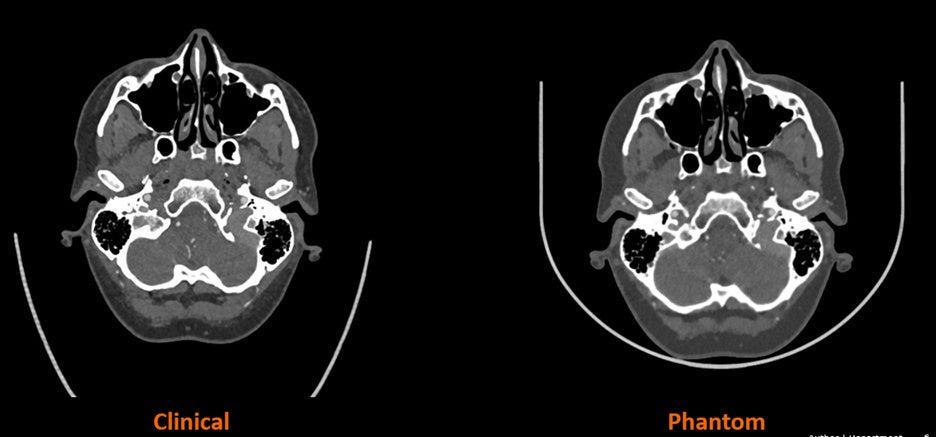

CTファントムとは、CTスキャナーの性能を評価・確認するために使用される特殊な装置です。人体の特定の特性をシミュレーションするように設計されており、放射線量や画質など、さまざまな中核的指標の評価を可能にします。また、キャリブレーションをサポートすることで、一貫したスキャナー性能を確保します。今回の共同開発では、ストラタシスのPolyJet™テクノロジーと独自のRadioMatrix™テクノロジーを組み合わせ、シーメンスヘルスケア社の高度なアルゴリズムを使って、スキャンした患者画像を人体構造の放射線透過性を持つ特定の材料特性に変換します。このソリューションにより、オーダーメイドのファントム製造が可能になり、これまで不可能であった患者固有の病態の完全なX線透視精度を備えた、超リアルな人体解剖学的特性の造形が可能になります。

この研究では、頭頸部領域の小規模な解剖学的構造ファントムの3D造形に始まり、徐々に大規模で複雑な解剖学的構造の3D造形が行われ、フェーズ1の評価項目である、心臓モデルや人間の胴体全体を完全なX線透視精度で3D造形するところまで到達する予定です。